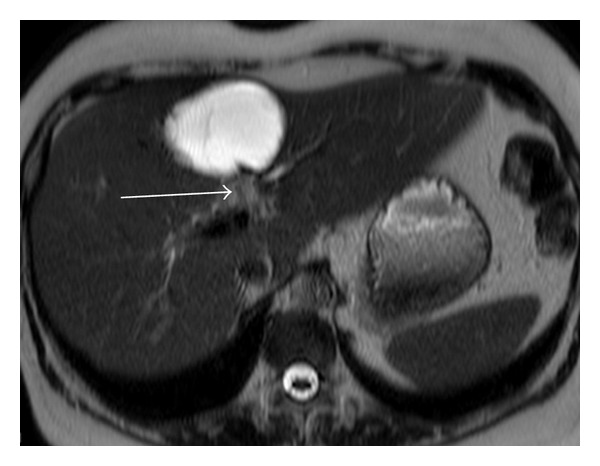

A 57-year-old woman was admitted to our hospital for investigation of epigastric and right hypochondriac pain and jaundice. Laboratory test results revealed liver dysfunction (cytolysis: alanine aminotransferase (ALAT) 922 IU/L; cholestasis: glutamyl transpeptidase (GGT) 1705 IU/L; alkaline phosphatase (PAL) 177 IU/L). The hydatid serology was negative. Liver MRI with cholangioMR was performed (Figures 1, 2, and 3). Axial T1 postgadolinium slices showed a cyst in the segment IV of the liver with a thick enhanced wall, axial T2 showed a one-centimeter tissular lesion behind the caudal portion of the cyst, and thick slice cholangioMR showed a mural nodule protruding in the left bile duct.

Figure 1.

Axial T1 after gadolinium. Cyst in the segment IV of the liver with a thick enhanced wall (arrow).